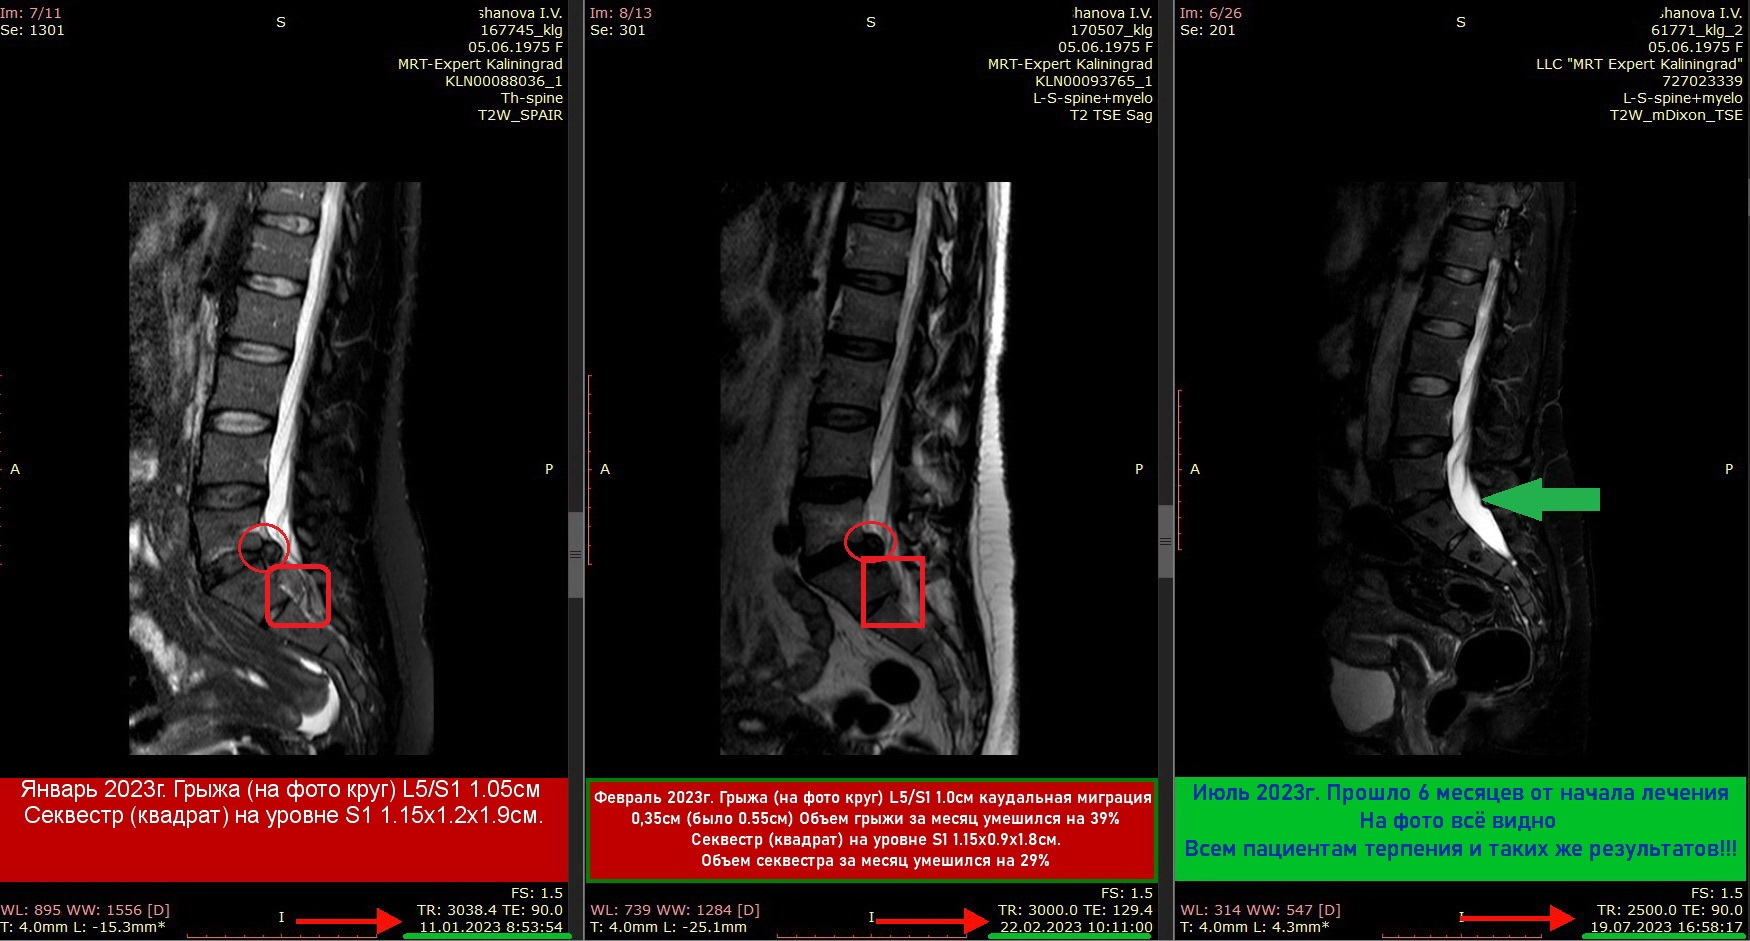

Примеры лизирования грыж

и секвестров

(Резорбция межпозвонковой грыжи)

выполненные главным врачем клиники Халанским Н.Н.